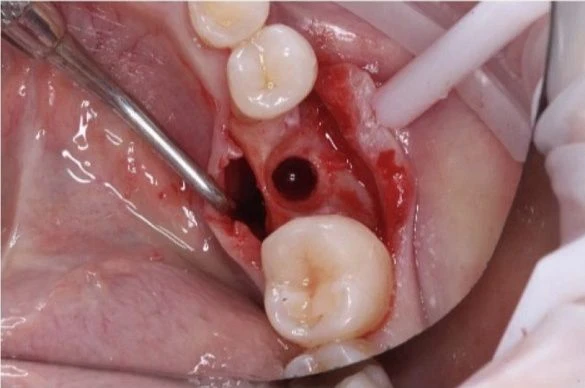

- Для реставрации жевательной поверхности зуба предпочтительным будет применение вкладки;

Как происходит процедура

Процедура микропротезирования включает следующие этапы: